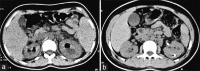

Background: Emphysematous pyelonephritis (EPN) is a necrotizing infection which results in gas within the renal parenchyma, collecting system, or perinephric tissue. A majority of cases occur in patients with diabetes mellitus (DM). In EPN, early aggressive medical treatment may avoid nephrectomy.

Results: All the study subjects had DM and all but two of them were females. The majority of our patients (61.5%) had extensive EPN (class 3 or 4) and majority (76.9%) had two or more bad prognostic factors. Escherichia coli was the most common causative organism involved in 50% of our cases. Twenty-three (88.5%) of our patients responded to conservative treatment, two required nephrectomy, and one expired on conservative treatment.

Conclusions: In this series of patients with EPN, all had DM, nearly all were women, and E. coli was the most frequently isolated pathogen. Nearly a third of our patients had bilateral disease. Despite the presence of two or more bad prognostic factors and extensive EPN (class 3 or 4) in a majority of our patients, conservative treatment afforded a striking success rate of 88.5%. We recommend early aggressive medical treatment and suggest that nephrectomy should be considered only if patients deteriorate or do not improve on conservative treatment.